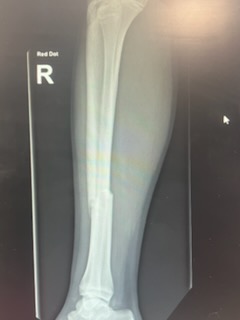

For your viewing pleasure, here are his before and after xrays!

Before:

You don’t need to be a doctor to diagnose the broken bone!